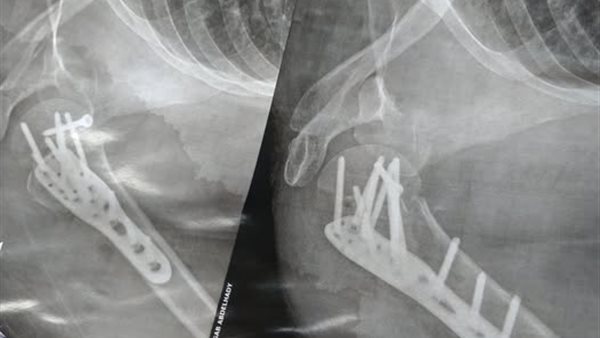

وأضافت: وأما وصلنا أول شارع المهداوي قالي بقولك إيه هاخد 50 جنيه مش هحلك فاهمة، وقولتله حضرتك قولت 30 قاللي هو كده قولتله مش ده اتفاق وحضرتك قولت 30 قاللي كده طيب اهووو، ولف لفة بالتوكتوك كأنه بيخمس وسحلني تحتيه فرمني، والنتيجة 11 مسمار وشريحة وقطع وتر ورد عظام الكتف بالجراحة وتمزق في الأربطة في رجلي، وجرح كبير في رجلي.